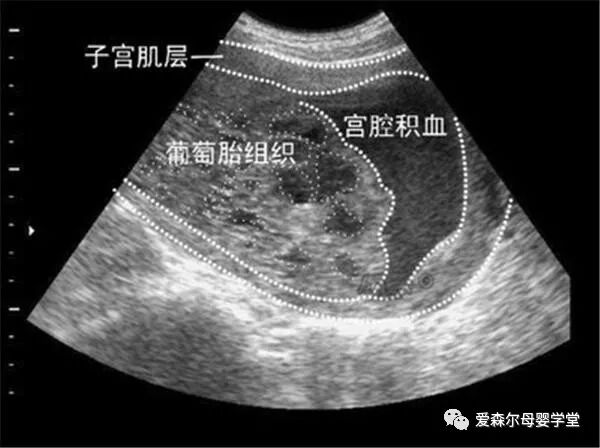

医生经过确诊后,告诉小敏的丈夫,小敏肚子里长的是葡萄胎。

葡萄胎,和葡萄无关,和胎儿更没有一点关系,它不过是妊娠后被胎盘绒毛,滋养形成了细胞增生,因为形状很像葡萄而得名。一般情况下,葡萄胎分为大约两类,一类是完全葡萄胎,另一类是部分葡萄胎。前者只有增生弥漫没有任何胚胎组织;后者虽可见胚胎或胎儿组织,但胎儿多为死亡状态,即使有活胎,也是畸形胎盘。

而小敏得的就是完全性葡萄胎。为了保证小敏的安全,医生建议立即手术治疗。